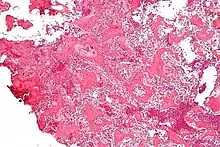

Histological findings

On histological examination, osteoid osteoma consists of a small (< 1.52 cm), yellowish-to-red nidus of osteoid and woven bone with interconnected trabeculae, and a background and rim of highly vascularized, fibrous connective tissue. Varying degrees of sclerotic bone reaction may surround the lesion. Benign osteoblastoma is virtually indistinguishable from osteoid osteoma. The usual appearance included a fibrovascular stroma with numerous osteoblasts, osteoid tissue, well-formed woven bone, and giant cells. The osteoblasts were generally small and regular in shape.[7]